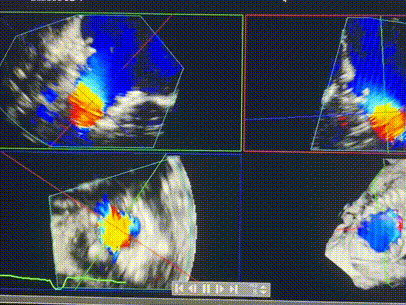

術(shù)中輸送器在超聲引導(dǎo)下調(diào)整位置

手術(shù)在全麻狀態(tài)下進行。術(shù)者采用經(jīng)右側(cè)頸靜脈入路的方式將輸送器送入患者心臟內(nèi),在TEE及DSA引導(dǎo)下調(diào)整輸送器頭端角度,使得輸送器與三尖瓣瓣環(huán)平面垂直。在輸送器進入右心室后釋放室間隔錨定裝置,而后釋放瓣葉夾持件(2個耳片結(jié)構(gòu))成垂直狀態(tài)。在TEE及DSA確定夾持件固定至三尖瓣葉根部且位于右室側(cè)后釋放人工瓣心房側(cè)盤片。隨后調(diào)整瓣膜同軸性以及室間隔錨定件位置(貼合室間隔),前推藏針管并固定,進而釋放室間隔錨定裝置,并再次確認瓣膜位置、穩(wěn)定性及同軸性,合攏輸送鞘后撤出輸送器,完成LuX-Valve Plus人工三尖瓣瓣膜的植入,僅殘余微量瓣周漏。且經(jīng)手術(shù)中心電生理團隊評估,病人的起搏器和ICD功能沒有受到影響。